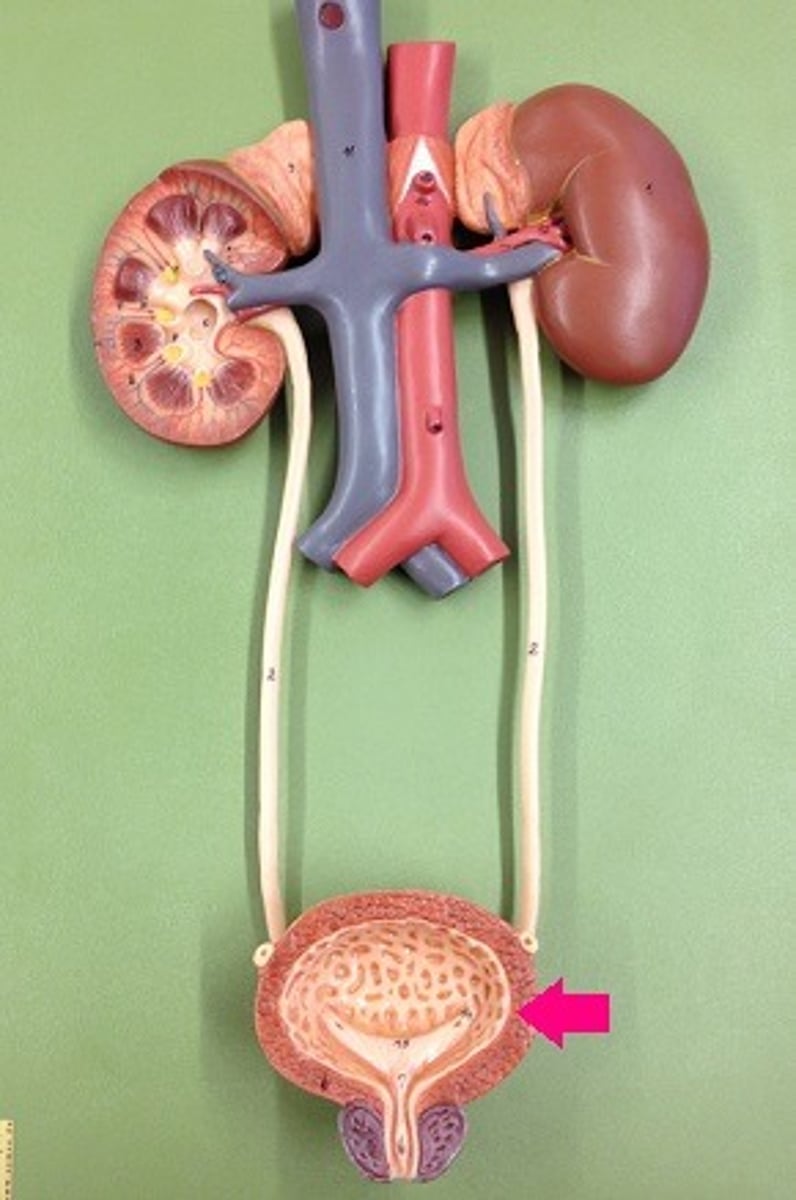

ureter

ureter

collecting duct

urinary bladder

urinary bladder

detrusor muscle

layer

internal urethral sphincter

bladder neck

external urethral sphincter

ureteric orifice

trigone of bladder

rugae

Urethra